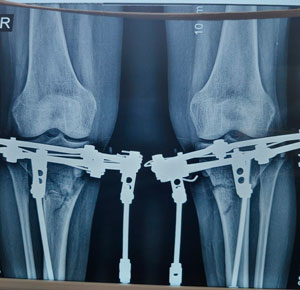

Дата операции - 04.07.2019г.

Дата снятия аппаратов - 10.10.2019г.

Срок сращения - 95 дней.